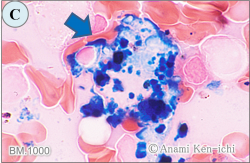

BM.1000

染色の種類と細胞の判別をお答えください。

C. 骨髄の鉄染色です。中央にはマクロファージが鉄顆粒(青色)を沢山貪食した像がうかがえます。この鉄顆粒は非フェリチン鉄(ヘモジデリン)が染まったものとされ、マクロファージの周囲に成熟赤芽球が取り囲んだ場合を赤芽球島とよび、赤芽球がマクロファージから鉄の補給をしているシーンともいわれます。本像では赤芽球の取り囲みは少ないようです。